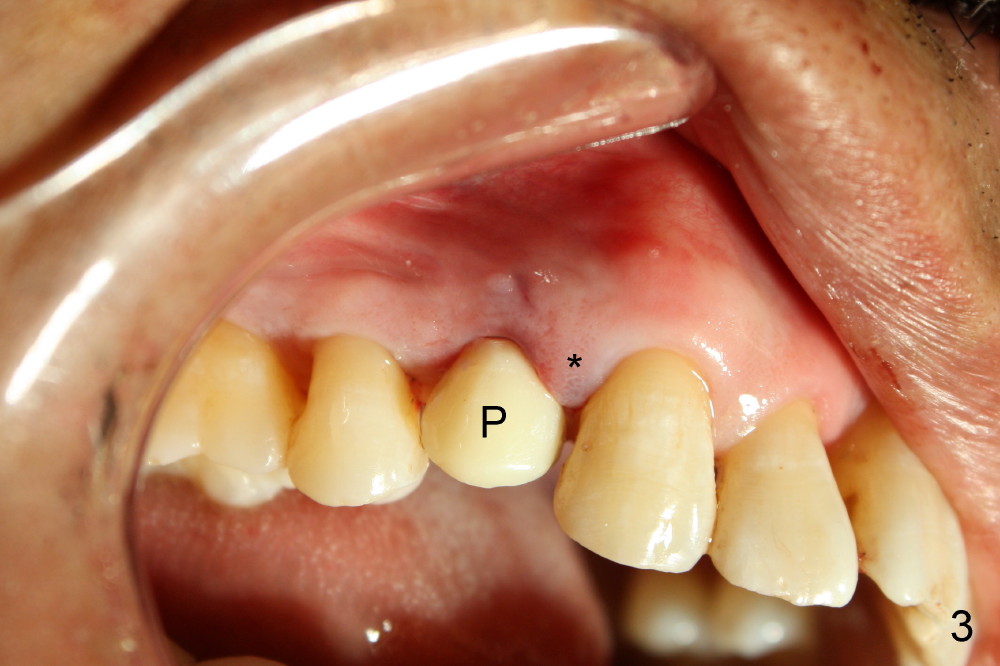

A provisional is fabricated immediately after extraction and implant and definitive abutment placement (Fig.3,4: P). The provisional hold the papilla in place (Fig.3 *). There is no occlusal contact with the opposing dentition (Fig.4 ^). The gingiva looks purplish due to difficult extraction. The tooth keeps fracturing while being extraction. The bone is dense. On the other hand, the dense bone helps achieve primary stability of the implant.